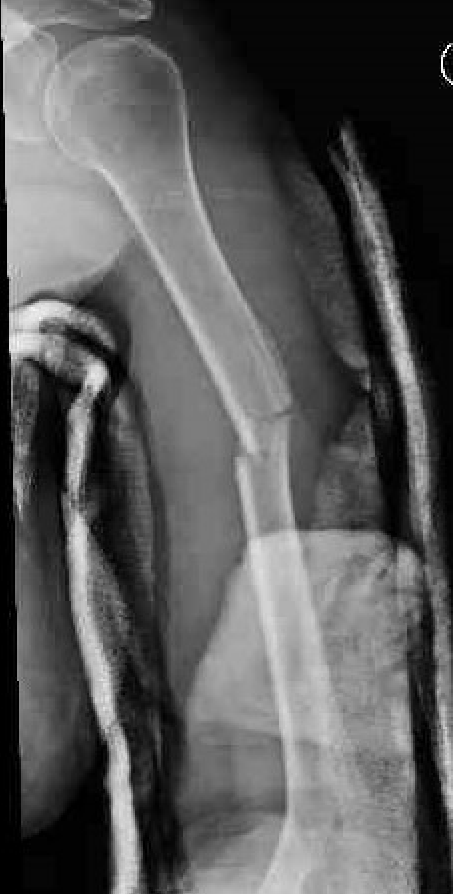

Management Nonunion Humerus Fractures

Background

Definition

Mean time to union is 13 weeks

No evidence of callous on xrays taken 6 - 8 weeks apart

Fracture patterns

- highest risk is transverse fractures

- proximal humerus shaft fractures also at risk due to displacing force of pectoralis and deltoid, and LHB may interpose